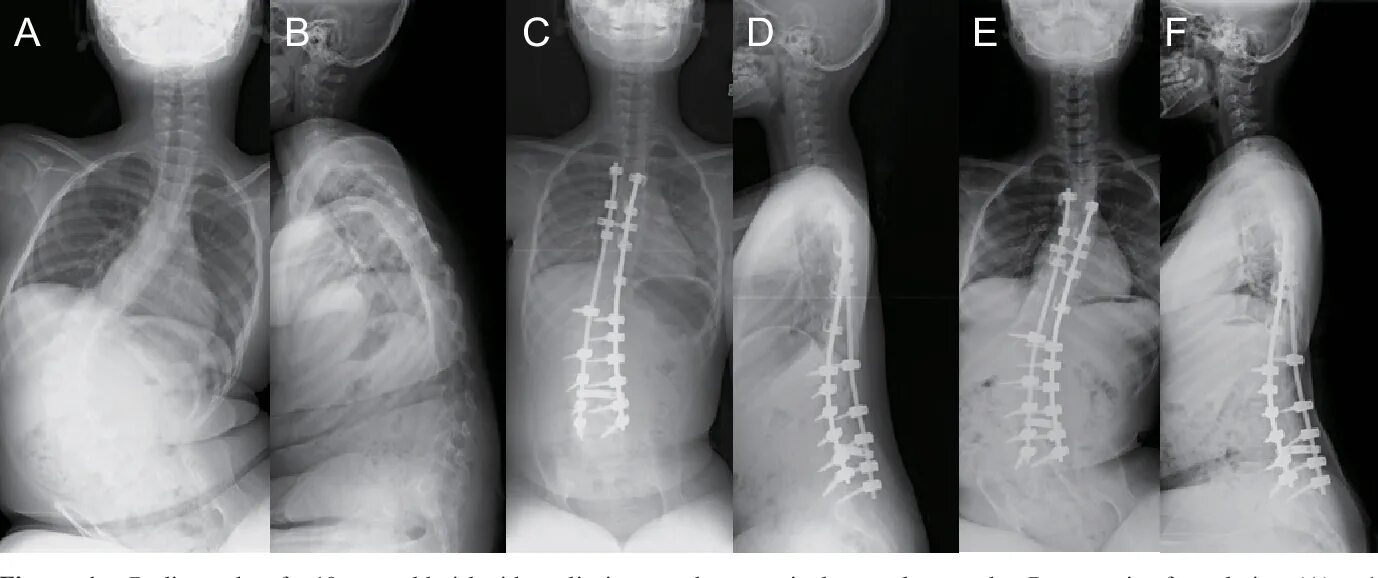

Симптомы спинальной мышечной